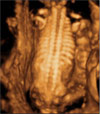

Ecografía 4D de un feto parpadeando en el tercer trimestre de embarazo

Es increíble ver esta ecografía de la última fase de la gestación, en la que percibimos claramente el parpadeo de un bebé. Éste acaba con la mano del bebé puesta sobre el ojo -seguramente le molesta el líquido amniótico- en un gesto fetal característico.